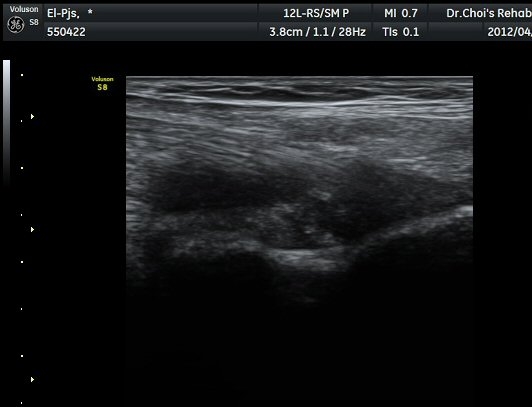

ŽÃËÀÚ¸¦ ÆÈ²ÞÄ¡ ¸»´ÜÀ¸·Î À̵¿ÇÏ´Ï À̵ιڱ٠ÈûÁÙÀÇ ºñÈÄ¿Í ÈûÁÙ ÁÖÀ§¿¡ Àú¿¡ÄÚ ¼ö¾×Àú·ù°¡ ]

°üÂûµÈ´Ù(±×¸² 2, 3, 4, 5). ŽÃËÀÚ¸¦ ¸»´ÜÀ¸·Î À̵¿ÇÒ ¶§ ŽÃËÀÚ¸¦ ¸Ó¸®ÂÊÀ¸·Î °æ»ç(tilting)½ÃÄѾß

À̵ιڱ٠ÈûÁÙ¿¡ Á÷°¢ ÀÇ ÃÊÀ½ÆÄ Á¶»ç°¡ °¡´ÉÇÏ¿© À̵ιڱ٠ÈûÁÙÀÌ °í¿¡ÄÚ·Î °üÂûµÈ´Ù.

À̵ιڱ٠ÈûÁÙ Á¾´Ü¸é°Ë»ç¿¡¼­ ÈûÁÙÀÇ ºñÈİ¡ °üÂûµÇ³ª ÈûÁÙÀÇ ¿ä°ñµ¹±â(radial tuberosity)

ºÎÂøºÎ´Â ºñµî¹æ¼ºÀΰøÀ½¿µ(anisotopic artifact) ¶§¹®¿¡ ¶Ñ·ÈÈ÷ °üÂûµÇÁö ¾Ê´Â´Ù(±×¸² 6).